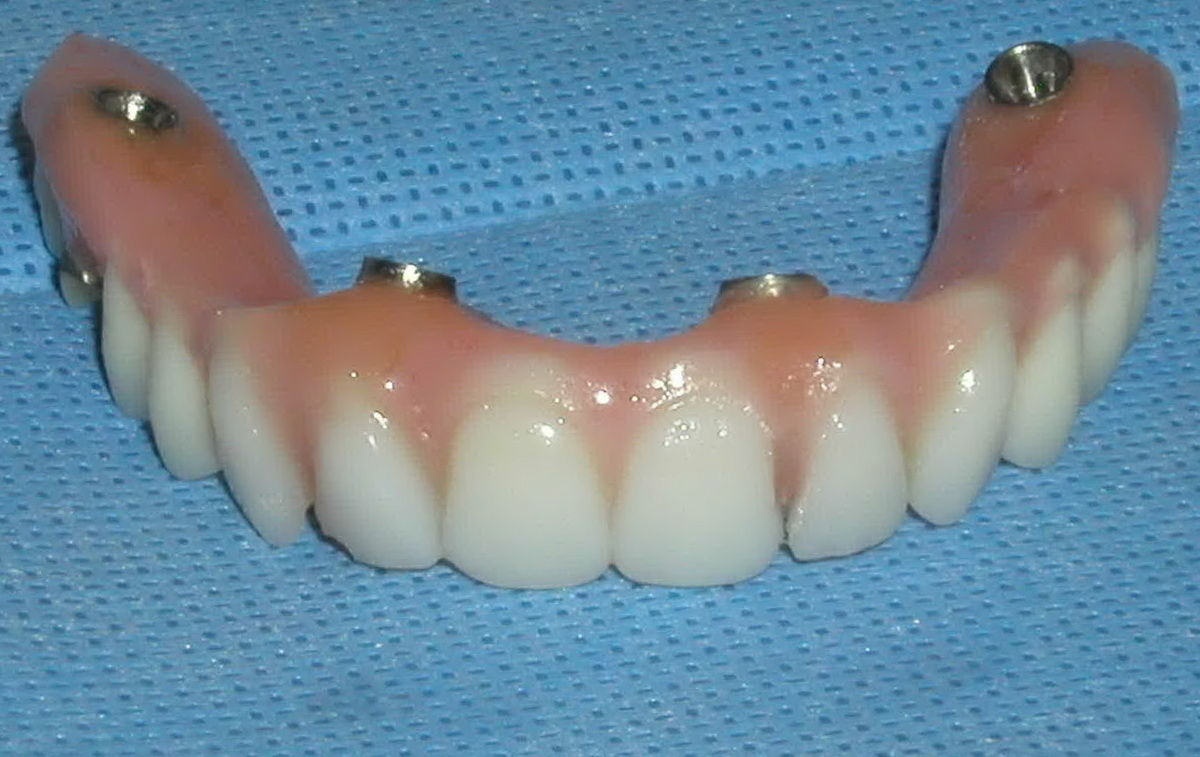

Nakon ugradnje implantata potrebno je vrijeme da bi se on integrirao, odnosno srastao sa kosti. Taj proces se naziva osteointegracija, a traje između 4 do 6 mjeseci. Kad u čeljusti uopće nemamo zubi možemo ih staviti u obliku fiksnog mosta na samo 4 implantata. To se zove sistem ALL-ON-FOUR.

Ugrađeni implantat zamjenjuje korijen ili korijene zubi koji nedostaju te postaje novi nosač navlake, mosta ili retencija za zamjenu ili lakše nošenje proteze.